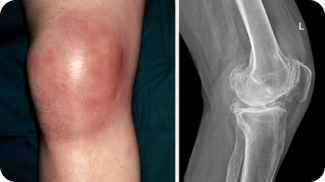

Бурсит

Болезнь сопровождается воспалением околосуставной сумки и развивается на фоне хронических травм у спортсменов и людей, работающих в тяжелых условиях. Травмы синовиальных сумок нередко сопровождаются присоединением инфекции, поэтому кроме тупых тянущих болей в коленных суставах после длительной ходьбы возникнет озноб, недомогание и прочие симптомы, свойственные бактериальным инфекциям.

У пациентов болят колени в районе чашечки при ходьбе и другой подвижности. Может появиться отечность и гиперемия кожи, а также локальное увеличение температуры. Лечение бурсита должно быть комплексным и включать прием противовоспалительных и антибактериальных средств. Также нужна иммобилизация сустава и прикладывание холода к нему.